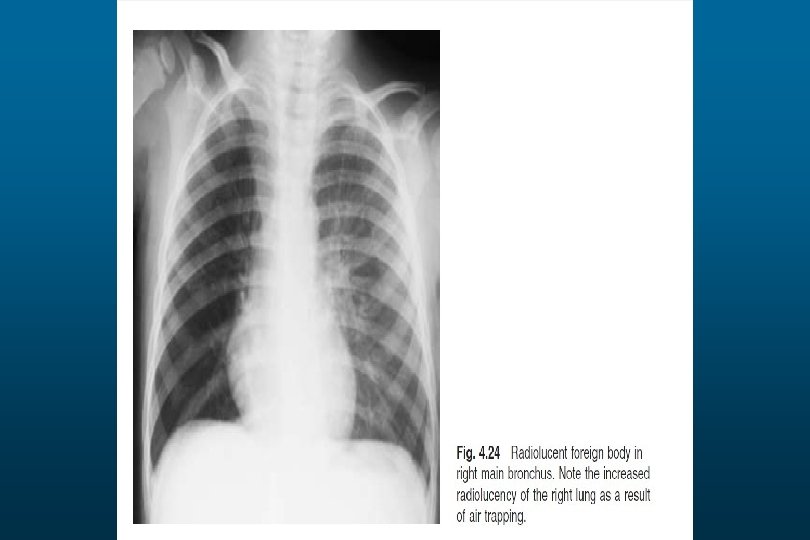

he right hemithorax is opaque There is a shift of the heart and trachea

he right hemithorax is opaque There is a shift of the heart and trachea away from the side ofo pacification This is characteristic of apleural effusion